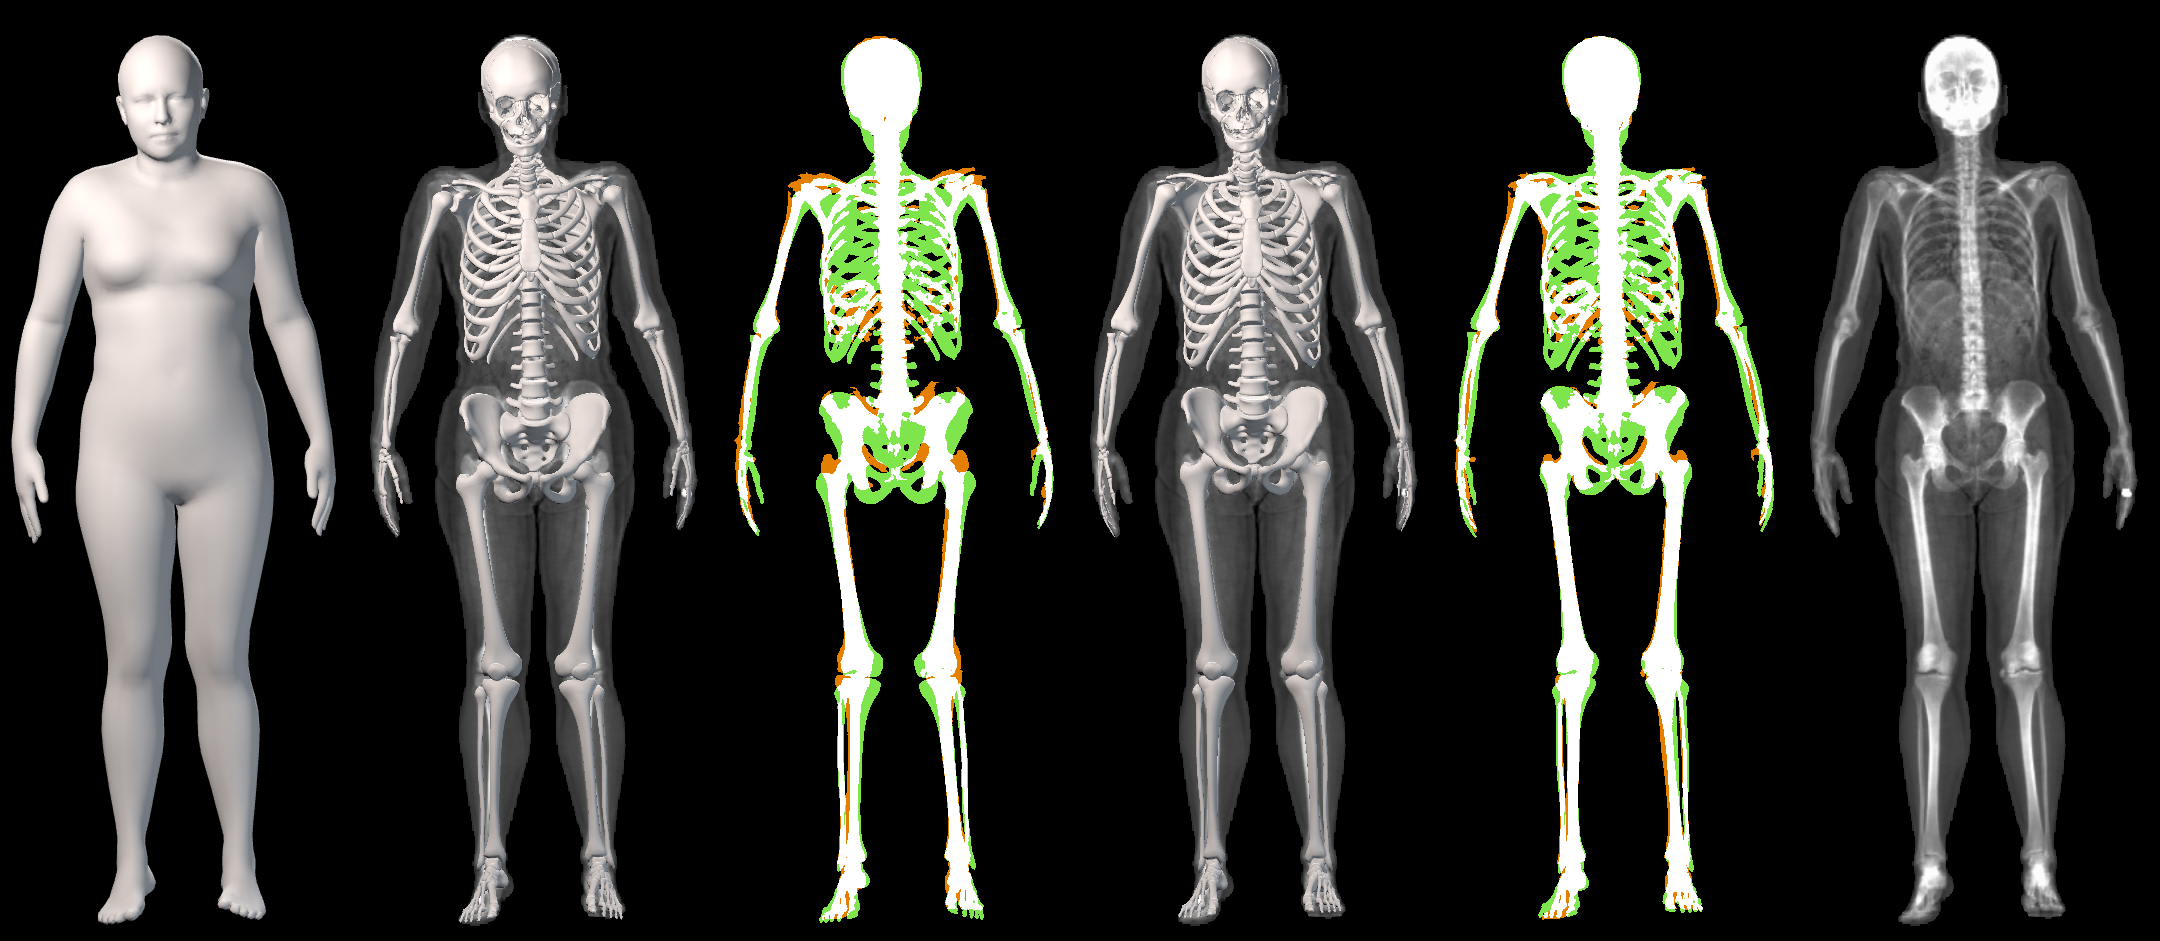

The key problem, however, is obtaining training data that simultaneously gives the inside and outside of the body in 3D. Most imaging technologies that simultaneously capture the inside and outside of the body use ionizing radiation, which is harmful to humans; e.g. Computed Tomography (CT) and X-rays. This means that such data is extremely limited, preventing learning-based methods. Our insight is to use dual-energy X-ray absorptiometry (DXA) data. DXA scans use low-dose X-rays to measure bone mineral density and body fat composition. The radiation level is so low that it is certified to be used on healthy patients for clinical studies, such as the UK Biobank [36]. In a DXA scan, two images are computed by combining two different energy levels: a soft-tissue image and a bone image (Fig. 2). In the silhouette of the body can clearly be seen, whereas reveals the structure and shape of the bones.

Creating the dataset has several steps: (1) we segment DXA images to get the silhouettes of the body and bones (Sec. 3.1), (2) we create synthetic skeleton silhouettes and use them to learn to predict landmarks (Sec. 3.2), (3) we register STAR [23] to the skin silhouette images (Sec. 3.3), (4) we create a custom skeleton model (Sec. 3.4) and register it to real skeleton binary masks (Sec. 3.5). Fig. 3 shows an overview of the dataset creation procedure.

From the input images (, ), we compute the corresponding skin and skeleton segmentation masks (, ). For the skin mask , we threshold . As some small artifacts remain, mainly due to pixels in the lungs with low intensity values, we detect the closed contours on the image and fill in small areas. In Fig. 2 we show pairs of input and the obtained mask .

In our work, we use a simple heuristic to automatically segment the bone tissue in the bone images: we assume that the brightest pixels in each image belong to bone tissue. We empirically set for the male DXAs and for the female. As small artifacts remain (earrings, clothing, etc.), we remove small connected components with an area less than 50 pixels. Note that we do not claim to segment all bone tissues in the DXA images. While our segmentations are coarse, they capture the structure and location of the bones inside the body (as shown in Fig. 2); this is what we need to fit a 3D skeleton to them.